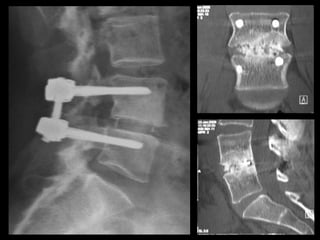

benefits Anterior interbody • anterior muscle-splitting only • minimal tissuetrauma indications • isolated degeneration • L5-S1 (L4-5) • no need to enter canal • thin, no previous major abdominal surgery FUSION FOR LOW BACK PAIN

benefits Transforaminal interbody • allows nerve decompression • allows alllevels • familiarity indications • not suitable for ALIF • nerve compression esp foraminal compression • correction of deformity